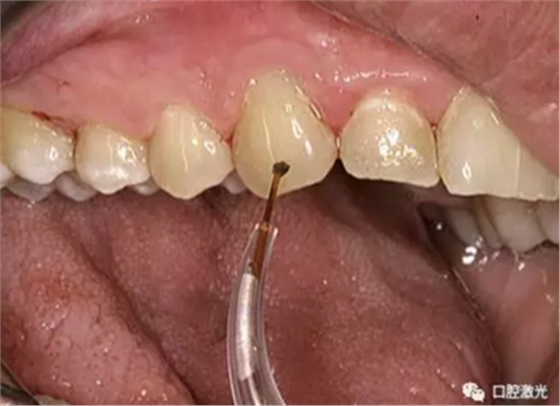

随后,使用半导体激光器,设置功率2.5W,50Hz脉冲输出。激光光纤尖伸入牙周袋内,在发射激光的同时,沿种植体表面滑动。需要经常目测检查光纤尖是否沾染了凝固的组织碎屑,并及时通过湿棉球清除干净。这样做的好处是防止光纤尖吸收激光能量导致组织温度过高。

每次治疗过程中,每颗种植体都需要做3个30秒钟的激光灭菌照射。在这30秒内,可以发射激光2-3秒,然后暂停2-3秒,累计激光照射时间须达到30秒。这样操作是为了严格控制组织的温度过高。由于细菌携带的色素对半导体激光吸收作用强烈,因此发炎细胞被破坏分解。但周围正常组织却不受高温影响,并且进行着激光生物刺激作用,实现一举两得的效果。